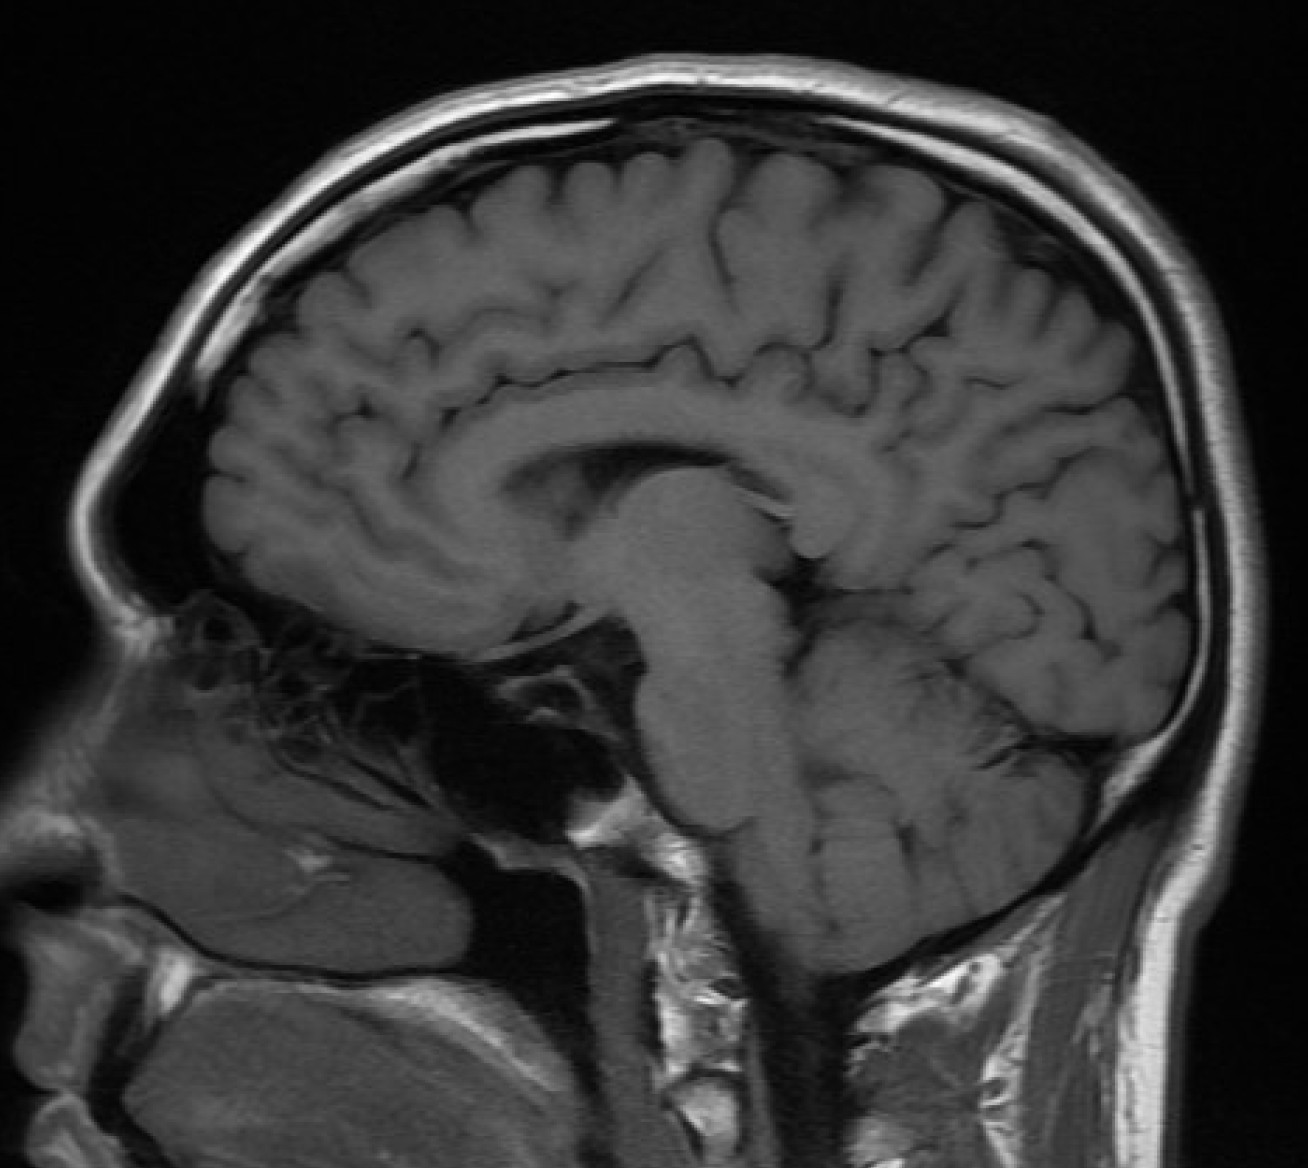

Brain

The work of the clinic will build on Imperial-led research which found that participation in elite adult rugby may be associated with changes in brain structure. (Credit: bucaorg (Paul Burnett) / Flickr)

The work will build further on Imperial-led research published earlier this year, which found that participation in elite adult rugby may be associated with changes in brain structure.

The study, which included 44 elite rugby players, found signs of abnormalities to the white matter of the brain, and changes in white matter volume over time – with almost half of the players involved having recently sustained a mild head injury while playing.

• Advanced Magnetic Resonance Imaging (3T MRI) using a range of highly-sensitive scanning techniques able to identify subtle structural and functional changes to the brain